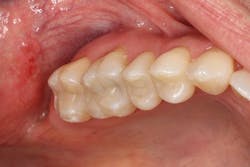

Figure 5: The restorations for Nos. 2 through 5 were completed with Tetric EvoCeram Bulk Fill in shade IVA.